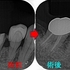

2026 EEdental SSY (3).jpg

クラウンを入れて2年半後にコアごとクラウン脱離

骨の所見を見ると、咬む力による問題+クラウンに強すぎる材料を使ってしまったここと推測

患者さんに謝り、もう一度根管治療からやり直させてもらいました。

ヘミセクションの際に自分がレジンコア作るべきだったと反省。。。

仮歯を入れて経過を見て行き

ようやく1年、骨もしっかり戻ってきてくれています。

この後、クラウンは弱目の材料で作っていこうと計画しています。